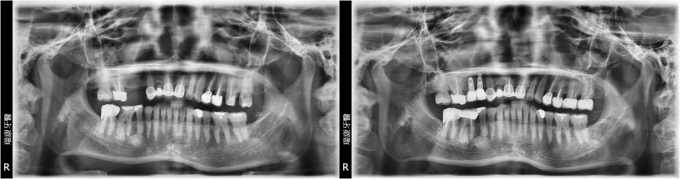

病患蘇小姐,65年次,上班族

- 主訴:想要重建右上缺牙區

- 治療計劃: 安排精密3D電腦斷層評估後,進行人工植牙, 三個月後進行APF增加角化黏膜 後續接出假牙基座印模製作正式假牙!

PS:患者表示:醫師很細心,解說詳細!

實例照片僅為資訊介紹及分享,效果可能因個人體質及保養方式不同而有所差異。